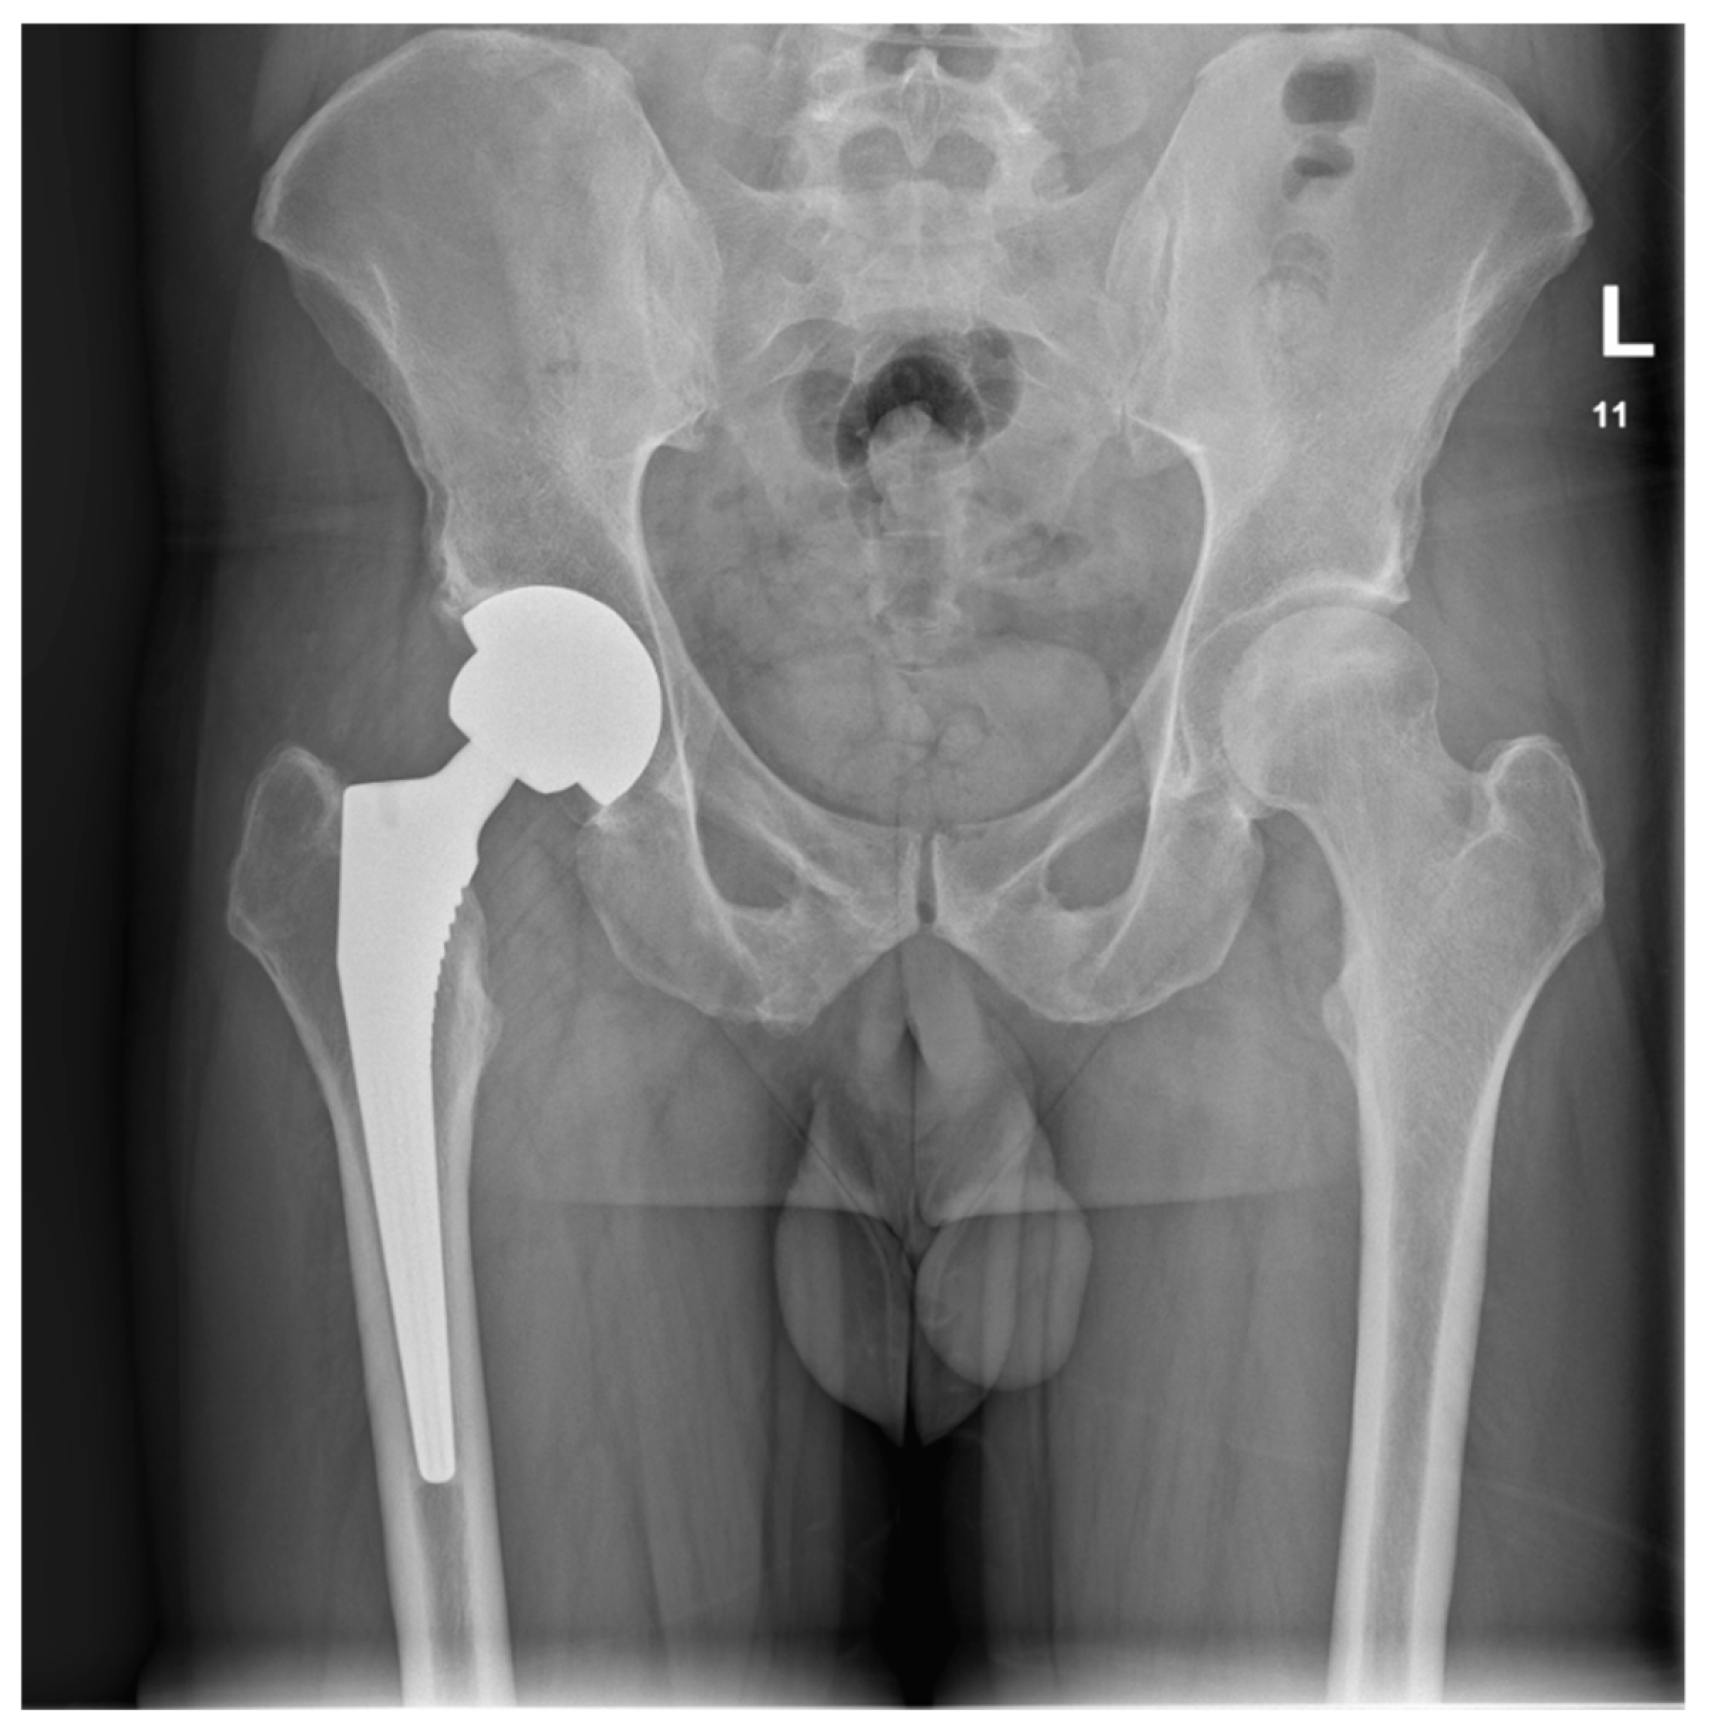

Upon the diagnosis of ONFH, the patient discontinued using steroid creams and was transitioned to non-steroidal moisturizers and a topical calcineurin inhibitor ointment (0.1% tacrolimus) for the management of AD. The patient received counseling on proper skincare practices and the potential long-term consequences of topical steroid overuse. The crescent sign was present at the anterolateral aspect of the right femoral head on plain radiographs, indicating Ficat and Arlet stage 3 ONFH. The crescent sign was a linear cleft due to a subchondral bone fracture, which may lead to the collapse of the femoral head. A total hip arthroplasty (THA) was indicated as a curative procedure for this patient’s hip illness, given the presence of femoral head collapse. He underwent a THA in June 2022. A direct lateral (Hardinge) approach was used. The acetabular component (Continuum, size 52, Zimmer Biomet, Warsaw, IN, USA) was placed using the line-to-line technique, while an uncemented Avenir, with a size 5 femoral stem (Zimmer Biomet, Warsaw, IN, USA) and a 36+4-sized head, was placed in the femoral canal (Figure 3).

Figure 3. Postoperative AP pelvis X-ray taken in June 2023, showing a stable THA.